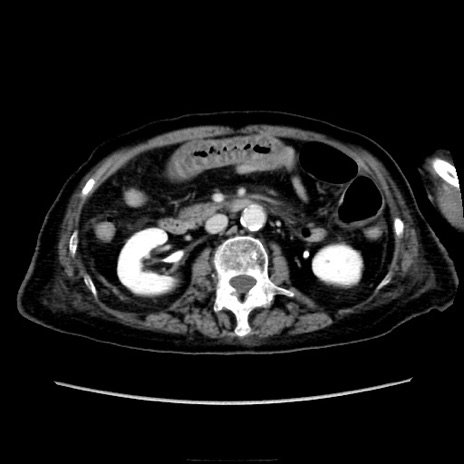

症例40(横断像)

【症例】90歳代女性

【主訴】腹痛・嘔吐

【現病歴】 食欲低下、嘔吐があり昨日他院受診。肺炎と診断され入院となる。入院後より腹部全体に圧痛あり。胃管留置され経過みていたが、症状持続するため、

当院転院となる。

【既往歴】胸椎圧迫骨折、胆石症

【身体所見】腹部:中央に激痛あり、圧痛あり、反跳痛不明

【データ】WBC 17100、CRP 18.82

横断像